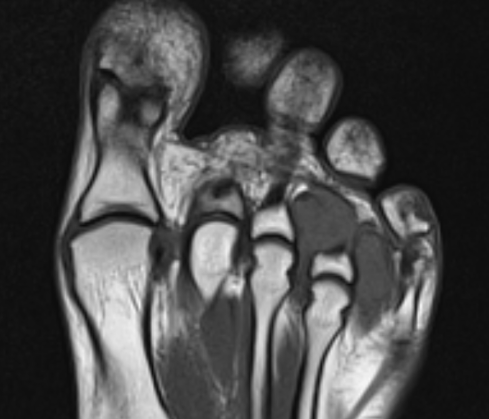

GCT flexor tendon sheath

GCT of tibialis posterior tendon sheath